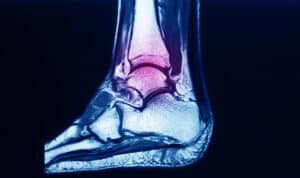

normal-hindfoot